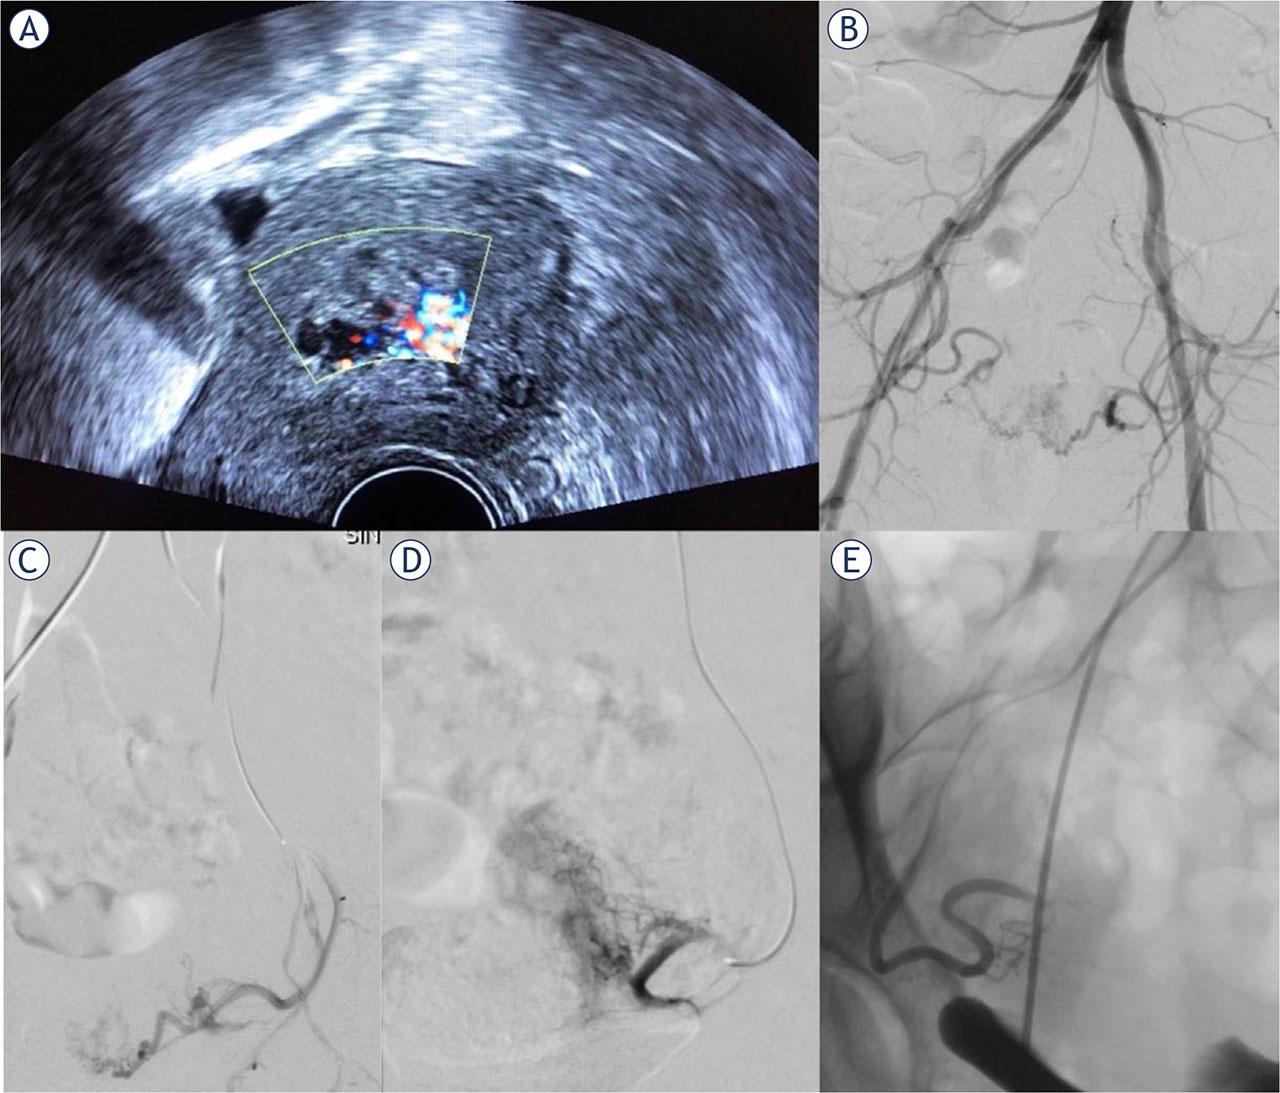

Figure 1.